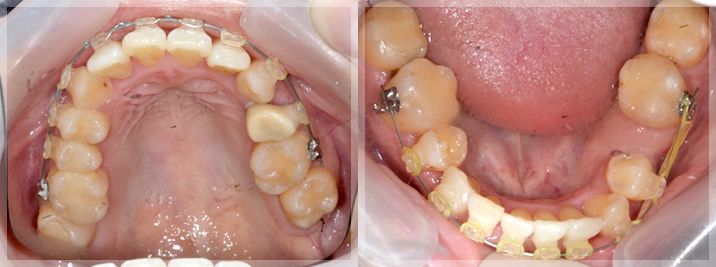

下顎の矯正開始

下顎にブラケットが着きました。前述のマウスピースで探った顎関節にとって最適な位置での噛み合わせを矯正治療中も維持していきます。